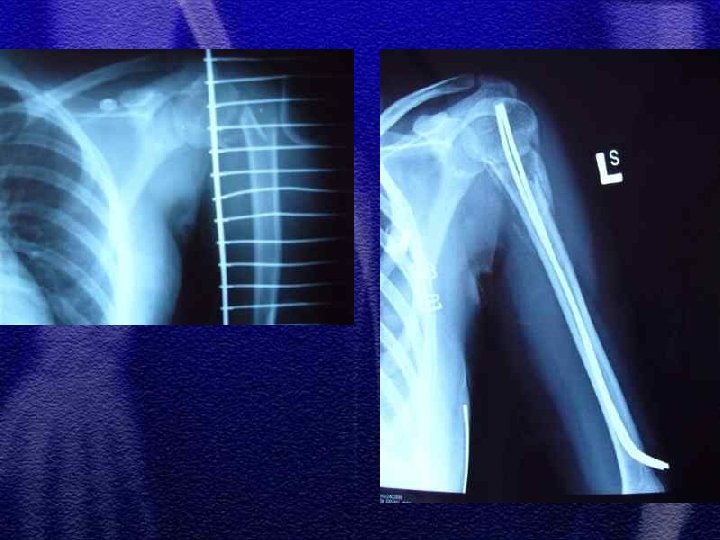

§ Noworodki – uraz okołoporodowy § Dzieci poniżej 3 roku życia oraz powyżej 12 r. ż. LECZENIE ZŁAMANIA T RZONU KOŚCI RAMIENNEJ § GIPS WISZĄCY § PODŁUŻNIK GIPSOWY + OPATRUNEK DESAULTEA § WYCIĄG SZKIELETOWY § LECZENIE OPERACYJNE - ZŁAMANIA OTWARTE POWIKŁANE USZKODZENIEM NACZYŃ I NERWÓW

§ Do 4 roku życia leczenie wyłącznie zachowawczewyciąg plastrowy lub szkieletowy w zależności od wieku § Większość złamań do 10 r. ż. - wyciąg szkieletowy ok. 3 tyg. , a następnie gips biodrowy od 3 do 6 tygodni w zależności od wieku § Leczenie operacyjne rozważa się po 10 roku życia a metody zespolenia to: Zespol, pręty Endera, Rusha, stabilizatory zewnętrzne

§ Częstym zjawiskiem występującym po złamaniach trzonu kości udowej u dzieci jest przerost (w zakresie uda) kończyny na długość § Przyczyną przerostu kończyny jest przekrwienie kości w wyniku złamania i nadmiernego pobudzenia chrząstek wzrostowych § Różnica długości kończyn może dochodzić do 2 cm

§ Noworodki i niemowlęta - tolerancja załamania osi 30 -40°, 1, 2 cm skrócenia § U dzieci starszych tolerancja załamania osi< 20°, przemieszczenia do boku przebudowują się § Lecząc wyciągiem szkieletowym (trwa to ok. 3 tyg. ) należy wystrzegać się nadmiernego rozciągnięcia odłamów (przerost na długość)